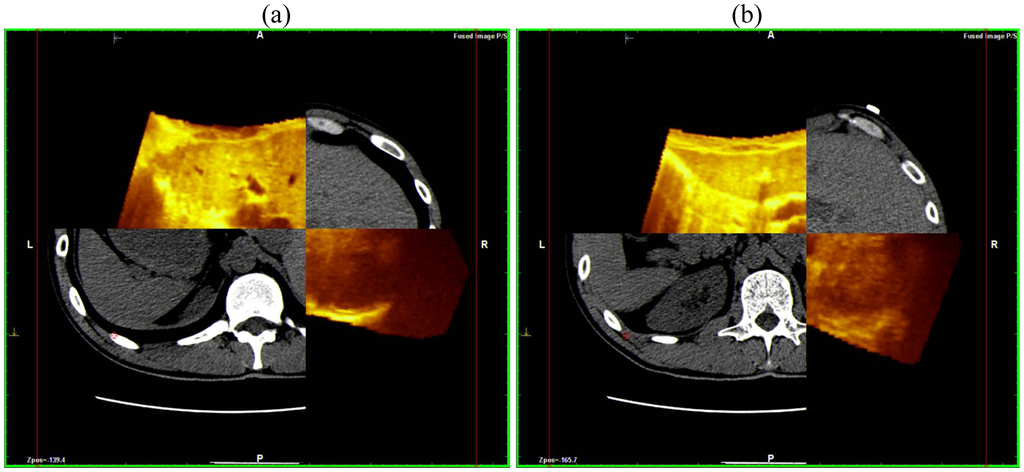

This scanning was possible both with conventional US and with contrast-enhanced US; the navigator system is furthermore able to perform a volumetric reconstruction of liver with CT scanning and to compare the two different volumes (US and CT) employing the fusion technique (Figure 3).

This superimposes each resliced layer of US and CT volumes showing both on the monitor: The post-processing fusion technique has consistently demonstrated that the CT and US 3-D reconstruction of the liver were exactly superimposable (Figure 4).